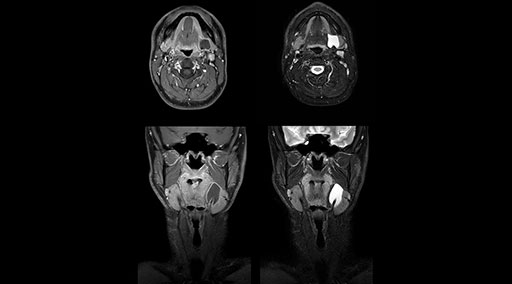

mDIXON TSE fat suppression helps DMG reduce repeats and supports diagnostic confidence

“Our DMG Lisle location includes a cancer center, so soft tissue neck scans, brachial plexus scans, and prostate scans are common. For these exams, mDIXON TSE provides excellent images with and without fat suppression all while helping us reduce repeats and work more efficiently,” Mr. Duffy says.

“With the 2-echo Philips mDIXON TSE the timing is short and the fatsat is very robust. The biggest thing is that you know your fat suppression will be good, even in thin patients or large patients that are off-center,” Mr. Sybesma says.

“mDIXON TSE raises our diagnostic confidence with its homogeneous

fat suppression. Neck exams and rheumatology patients are two examples where mDIXON TSE is especially useful,” Dr. Kaakaji says. “For us it’s also an efficiency boost in exams where we need pre and post T1-weighted images with great fat suppression.”